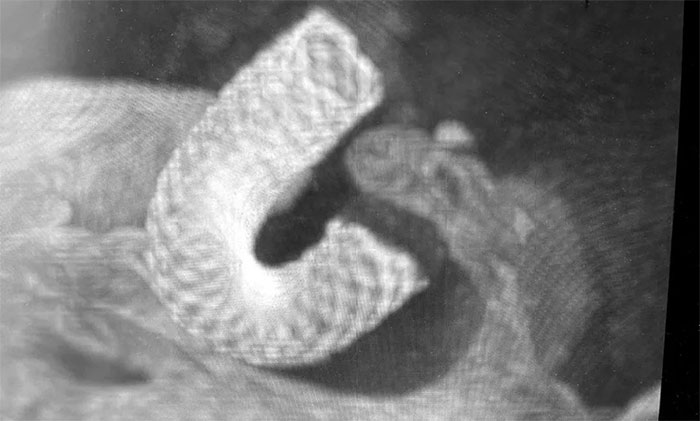

经充分完善术前准备,席刚明教授在麻醉科和介入手术室紧密配合下,开展右颈内动脉眼动脉段动脉瘤血流导向装置(Pipeline)置入术。手术历时两个小时,顺利“拆除”了埋在患者脑子里的“不定时炸弹”。

▲ 造影显示血流导向装置贴壁良好

术后,患者无新发神经功能缺损,余志良主任进一步为患者开展活血化瘀、改善脑循环、营养神经等中西医结合对症治疗,头痛症状基本消失,于近期康复出院。